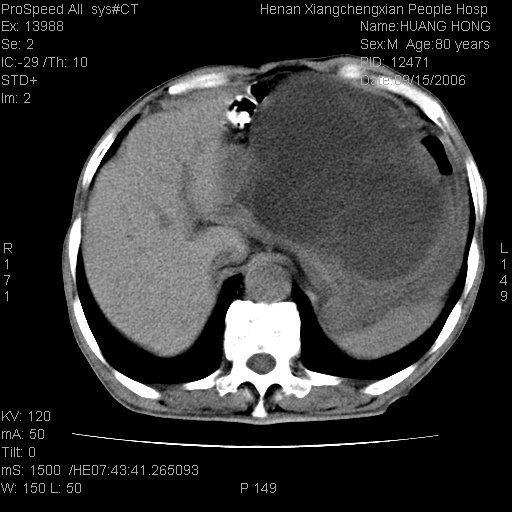

患者, 男, 80岁, 发现上腹部包块1年余,无其它不适.2006-9-14ct片是喝水后扫描2006-9-15ct片没喝水扫描![]() ![]() ![]() ![]() ![]() ![]() ![]() ![]() ![]() ![]() ![]() ![]() ![]() ![]() ![]() ![]() 以上是喝水片 以下是空腹片 ![]() ![]() ![]() ![]() ![]() ![]() ![]() ![]() ![]() ![]() ![]() ![]() ct:胰腺前方、肝脏与胃之间可见巨大类圆形囊性低密度影,大小约152mmx145mmx118mm,上缘平t11椎体上缘,下缘平l3椎体下缘,密度均匀,ct值15hu,其内呈多房分隔,囊壁薄且光滑,边界清晰,周围组织及器官明显受压。肝脏实质内未见异常密度影,胆囊未见异常,胰腺密度未见异常,脾脏大小、形态及密度未见异常,腹膜后间隙未见肿大淋巴结影。 印象:胰腺前方、肝脏与胃之间巨大类圆形囊性低密度影.性质待定。多考虑:.肠系膜巨大囊肿。 守望可可西里发言:支持楼主,考虑肠系膜囊肿,多为小肠系膜。 ysxyy发言:我总觉得这个病人虽然很像肠系膜囊肿,但还是应该强化一下; 下面这几幅图里肿块和主动脉的关系不太清,不知能否除外血管性来源? ![]() ![]() ![]() 病理结果:横结肠系膜间叶瘤.部分区域间质细胞增生活跃. 病理图片 ![]() 良性间叶瘤:是指由两种或两种以上的间叶组织所构成的混合性肿瘤.肿瘤仅发生在腹膜后和肠系膜,.前者较后者多发.良性间叶瘤常发生在肾或四肢,腹膜后较少见,各年龄均可发病.女多与男,预后较好,但术后易复法. 恶性间叶瘤:由两种以上恶性间叶组织成分组成. 光镜:肿瘤由脂肪/血管/平滑肌构成. 原贴地址: http://www.radinet.com.cn/forum_view.asp?forum_id=4&view_id=16217 ok |